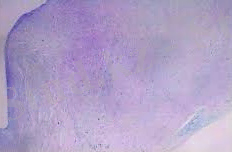

Фибриноидты ісіну

Фибриноидты ісіну-бұл ақуыздың (коллаген, фибронектин, ламинин) ыдырауына және ГАГ деполимеризациясына негізделген дәнекер тінінің терең және қайтымсыз ыдырауы, бұл оның негізгі заты мен талшықтарының жойылуына әкеледі, тамыр өткізгіштігінің күрт жоғарылауымен және фибриноидтың пайда болуымен бірге жүреді.

Фибриноид-ыдырайтын коллаген талшықтары мен негізгі заттың ақуыздары мен полисахаридтері, сондай-ақ плазмалық қан ақуыздары мен бұзылған дәнекер тінінің жасушаларының нуклеопротеидтері нәтижесінде түзілетін күрделі зат. Фибриноидтың міндетті компоненті-фибрин.

Микроскопиялық түрде коллаген талшықтарының байламдары біртекті, эозинофильді болады (қышқыл радикалдардың плазмалық ақуыздармен бітелуіне және рН ортаның сілтілік жағына ауысуына байланысты), күрт шикі болады, бұл олардағы гликопротеидтер санының едәуір артуын көрсетеді. Фибриннің түсі әрқашан оң болады, бірақ оның қарқындылығы өзгереді. Толуидин көкімен боялған кезде Метахромазия жоқ. Бұл толықтай жойылуына байланысты.

Фибриноидты ісіну пайда болатын макроскопиялық органдар мен тіндер аз өзгереді.

2. сурет. Фибринойдты некроз (Г - Э)

Фибриноидты ісінудің нәтижесінде кейде дәнекер тінінің толық жойылуымен сипатталатын фибриноидты некроз дамиды. Некроз ошақтарының айналасында әдетте макрофагтардың реакциясы байқалады. Болашақта деструктивті фокусты тыртықты дәнекер тінімен (склероз) немесе гиалинозмен алмастырады.

Фибриноидты ісінудің мәні. Фибриноидтық ісіну бұзылуға және көбінесе органның жұмысын тоқтатуға әкеледі (мысалы, фибриноидтық өзгерістермен және гломеруланың артериолалары мен капиллярларының некрозымен сипатталатын қатерлі гипертониядағы жедел бүйрек жеткіліксіздігі. Фибриноидты некроздың нәтижесінде пайда болатын склероз немесе гиалиноз жүрек клапандарының функциясының бұзылуына (жүрек ақауларының пайда болуына), буындардың қозғалғыштығына, люменнің тарылуына және қан тамырлары қабырғаларының икемділігінің төмендеуіне және т. б.